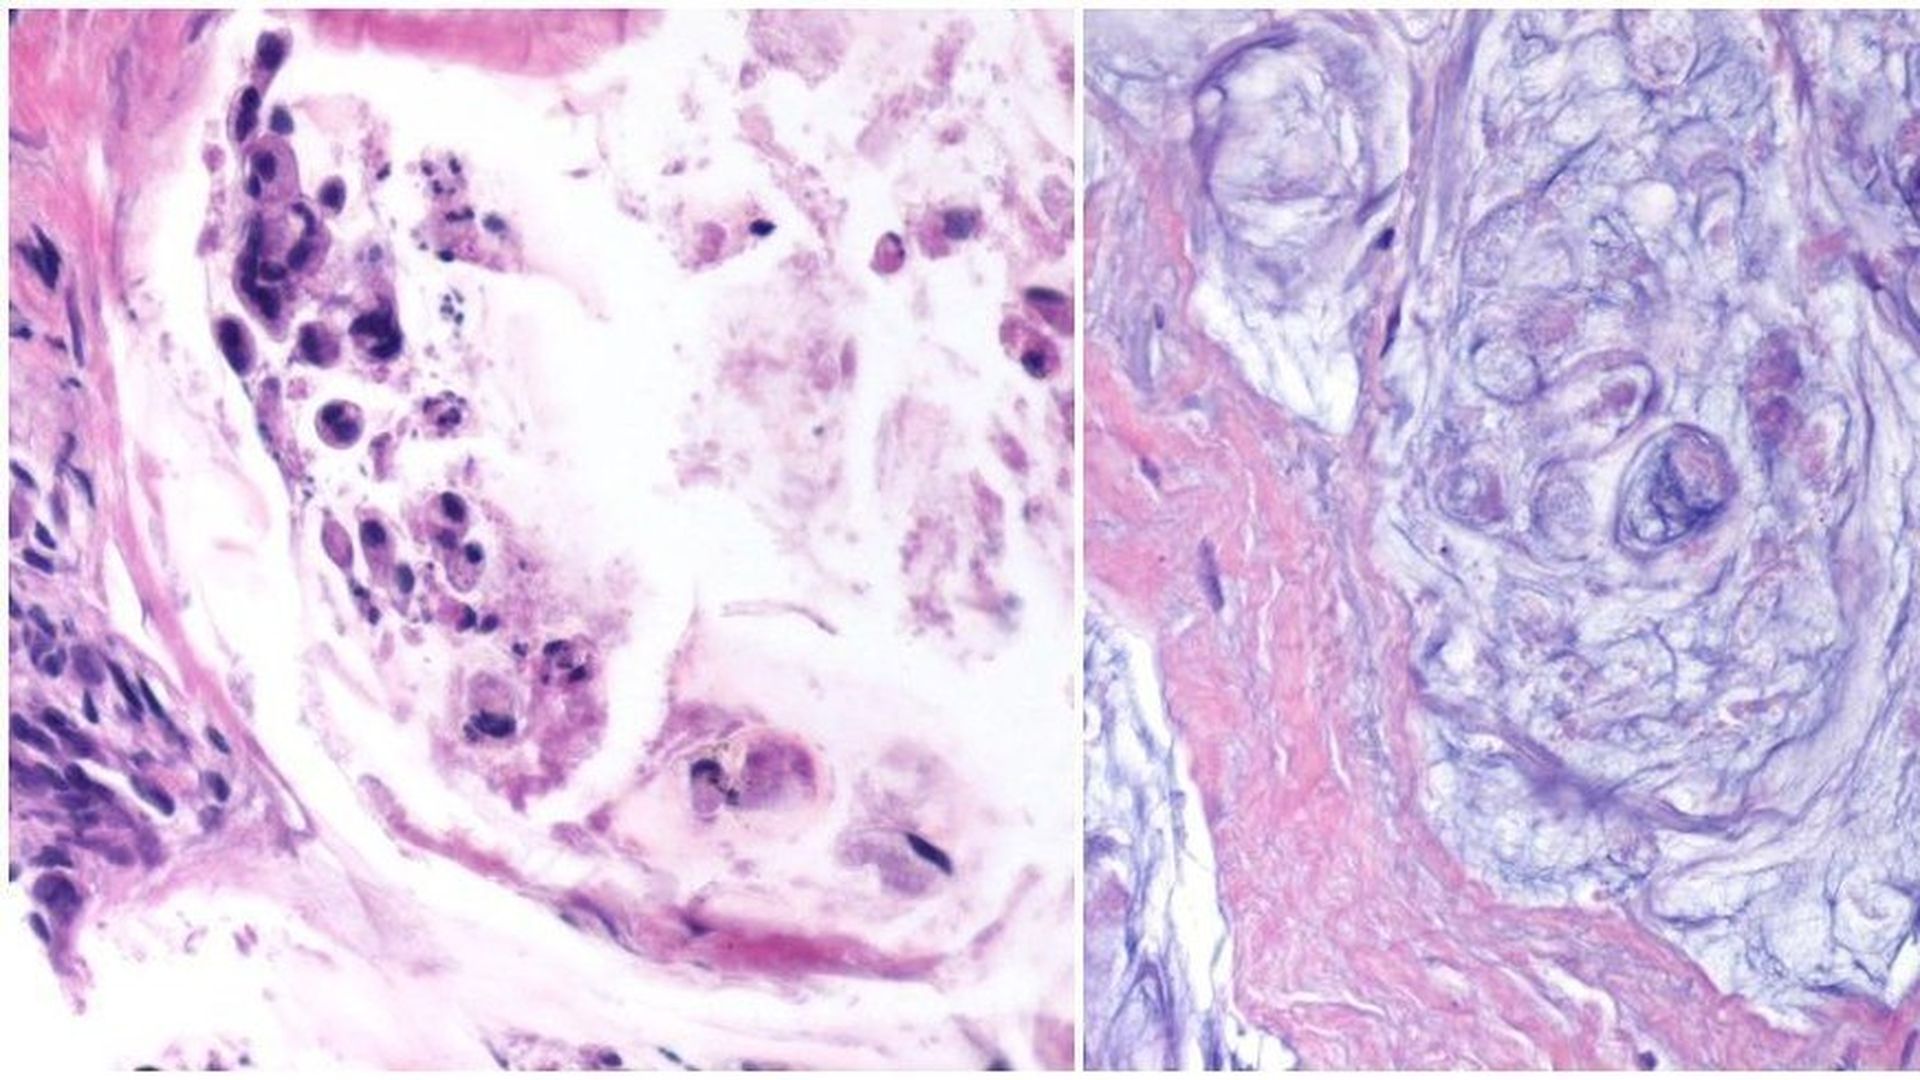

Live cancer before treatment (l)/ Dead cancer after treatment (r)

A new study found tumors with a certain marker can be targeted by the drug pembrolizumab regardless of where they are in the body. The drug's success led the FDA to grant it accelerated approval in May — as many as 60,000 adults and children could benefit per year.